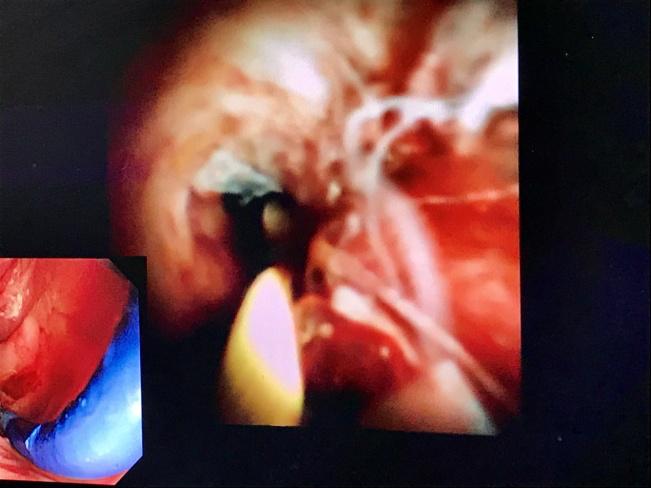

治疗中,由于老太太年龄大、结石大、病情重,给手术造成了很大的难度,而且患者肿瘤标志物明显升高,在与患者家属充分沟通后,为进一步排除恶性可能,宿慧大夫叮嘱患者三个月后复查。复查时,我们为患者再次行ERCP,并于术中应用Spyglass直视探查胆管,明确了狭窄处存在表浅溃疡,之后活检病理确认为肉芽组织。在导管室全程导引下,手术圆满成功,整台手术仅耗时约20分钟,并放置了鼻胆管引流。

另一名患者因梗阻性黄疸来诊,入院时胆红素显著升高,CT检查提示胆总管上段狭窄。患者情况较差,消化内科ERCP团队遂急诊放置鼻胆管引流,待患者状况及黄疸改善后再行ERCP检查。术中Spyglass直视探查胆管,证实胆总管上段存在明显狭窄,表面溃疡,结节状增生,质地脆,活检证实为恶性病变。

Spyglass系统全称为“经口胆道子镜光纤直视系统”,是一种电子胆道子镜,可对胆管内病变进行直视观察,高清高分辨率显示病变、并精准指导活检,对于胆管狭窄的诊断具有重要意义。北京世纪坛医院消化内科现已开展多例Spyglass操作,使医院胆管疾病的内镜下诊治达到国内先进水平,助力临床的精准诊治。